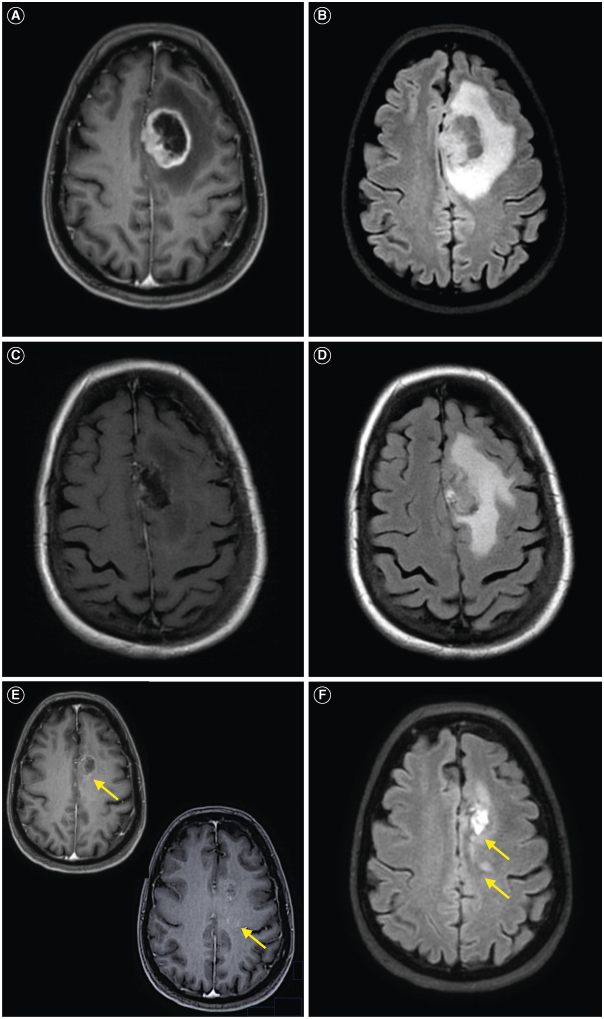

Glioblastoma is the most common malignant primary brain tumor. Despite its infiltrative nature, extra-cranial glioblastoma metastases are rare. We present a case of a 63-year-old woman with metastatic glioblastoma in the lungs. Sarcomatous histology, a reported risk factor for disseminated disease, was found. Genomic alterations of TP53 mutation, TERT mutation, PTEN mutation, and +7/-10 were also uncovered. Early evidence suggests these molecular aberrations are common in metastatic glioblastoma. Treatment with third-line lenvatinib resulted in a mixed response. This case contributes to the growing body of evidence for the role of genomic alterations in predictive risk in metastatic glioblastoma. There remains an unmet need for treatment of metastatic glioblastoma.

Abstract Image